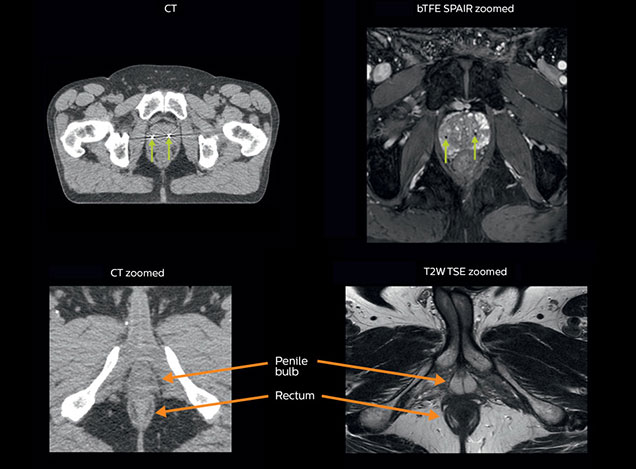

Visualizing critical structures with MRI before prostate radiation therapy

A 63-year-old patient with prostate cancer, cT3bNxM, Gleason 7, underwent MRI on Ingenia 3.0T MR-RT before radiation therapy.

Intraprostatic lesions are visible on the bTFE MR image, but not on the CT image. MRI shows excellent soft-tissue contrast for the visualization of critical structures like the rectum and penile bulb.

Fiducial markers (green arrows) are used in registration of MR images to CT, to transfer the MR-based delineations onto the CT image dataset.